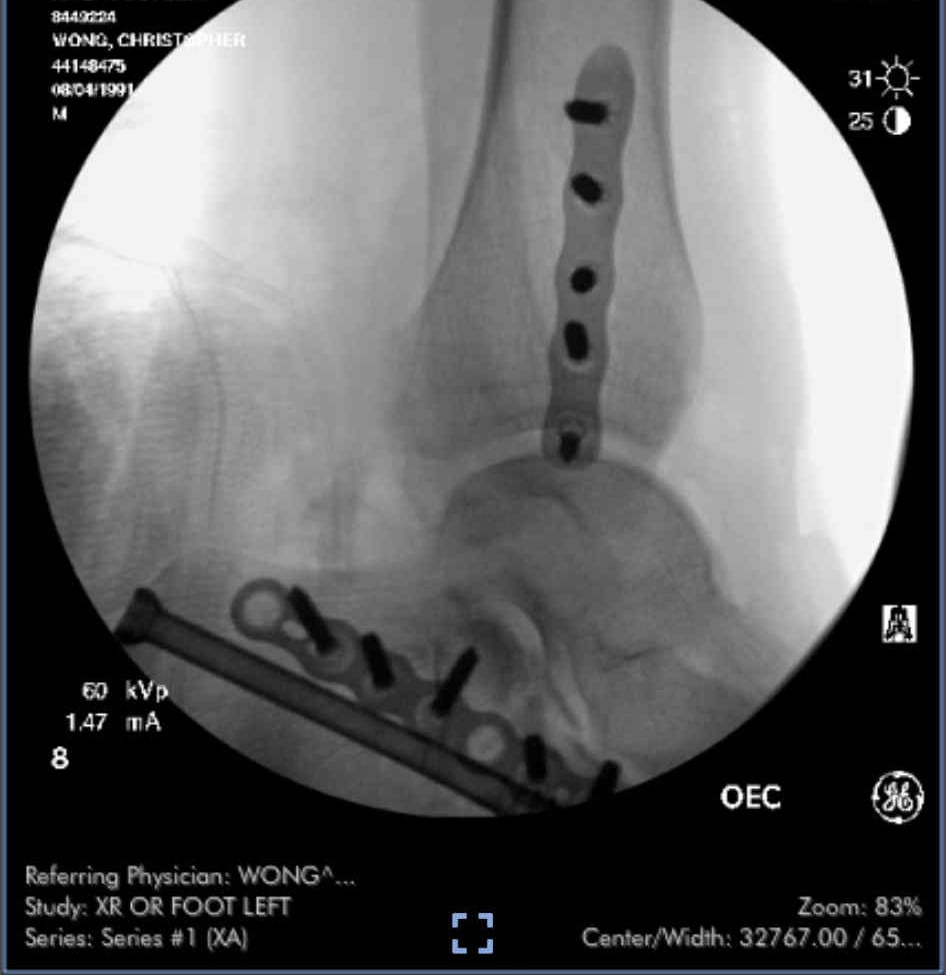

Our dear friends’ son, Holland, was on his motorcycle when he was broadsided by a car in a terrible accident that severed his foot. Surgeons managed to reattach it, but it’s still uncertain whether it can be saved — and he will require multiple additional surgeries if he’s able to keep it. He now faces months of surgeries, rehabilitation, and recovery — and is devastated beyond belief.